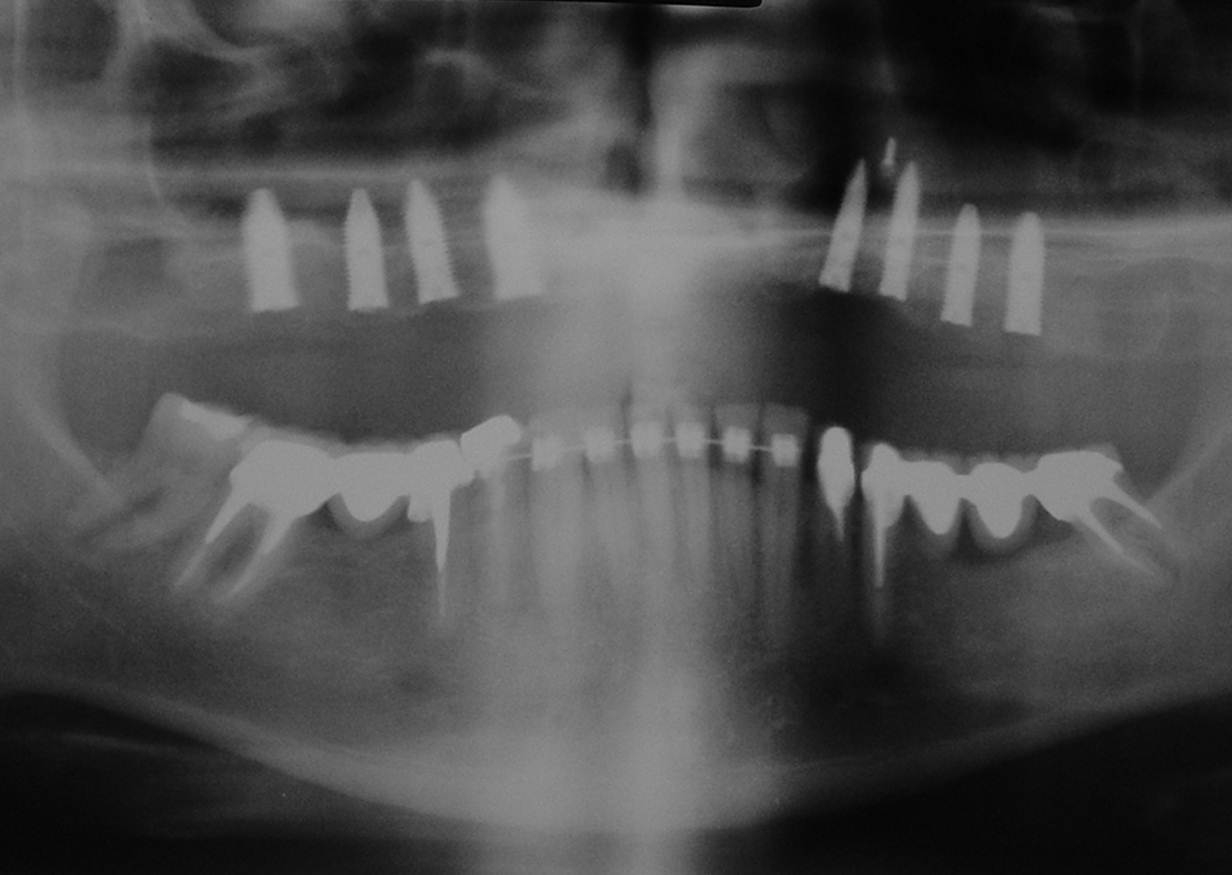

Raio X com 08 implantes Cone Morse instalados na maxila - Clínica Cliniface

Raio X com 08 implantes Cone Morse instalados na maxila